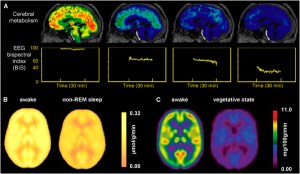

In allegato alcune immagini dal Web del cervello in tutte le sue fasi interessate.